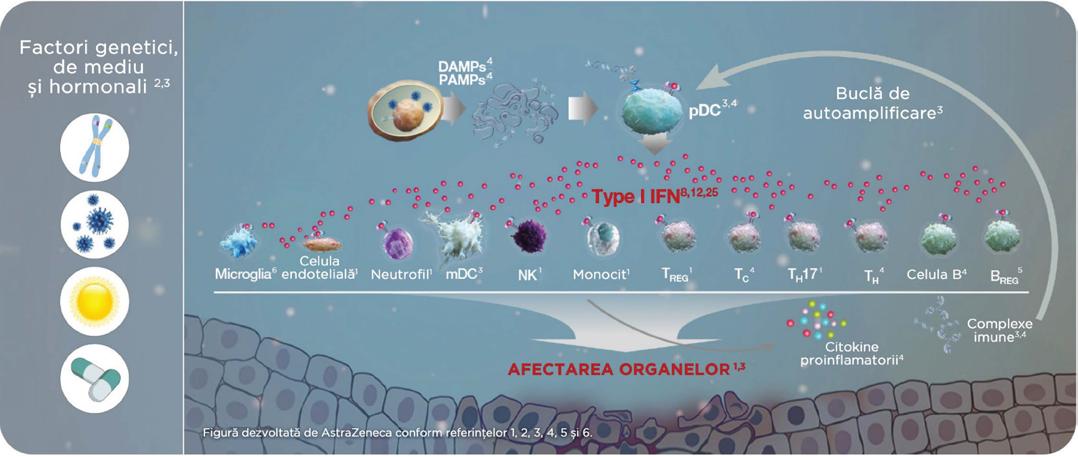

INTERFERONUL DE TIP Ielement cheie in etiopatogenia lupusului eritematos sistemic (LES).

lnterfero nul de ti p I este o citokina im porta nta , atat in imun itatea in nascuta, cat $i in cea do bandita; perturba rile celor do ua ti puri de imun itate contr ibuie la pro ces ul de autodistrugere din LES, un pro ces ci clic in ca re interfero nul de ti p I are un ro l centr al.

ROLUL INTERFERON I IN LES

Ca raspuns la interferonul de tip I, celulele sistemului imunitar atat inascut, cat $i dobandit eliberea za o cascada de citokine proinf lamatorii $i autoanticorpi, formand acid nucleic care contine complexe imune ce pot initia leziuni tisulare $i afectarea organelor 7

B REG = B regulatory; DAMP = damage-associated molecular pattern; IFN = interferon; mDC = myeloid dendritic cell; NK = natural kille; PAMP = pathogen-associated molecular pattern; pDC = plasmacytoid dendritic cell; SLE = systemic lupus erythematosus; TC cytotoxic T; T H = T helper; T H 17 = T helper 17; T REG = regulatory T.

Referinte: 1. R6nnblom L, Leonard D. lnterleron pathway in SLE: one key to unlocking the mystery of the disease. Lupus Sci Med. 2019;6(1):e000270; 2. Buyon JP, Cohen R Merrill JT, et al A highlight from the LUPUS 2014 meeting: eight great ideas. Lupus Sci M 20152(1):e000087; 3. Liu Z. Davidson A Taming lupus - a new understanding of pathogenesis is leading to clinical advances. Nat M 201218(6):871-882; 4. Chan VS, Nie YJ, Shen N, Van S Mok MY, Lau CS Distinct roles of myeloid and plasmacytoid dendritic cells in systemic lupus erythematosus. Autoimmun Rev. 2012;11(12):890897; 5. Menon M, Blair PA, Isenberg DA, Mauri C. A regulatory feedback between plasmacytoid dendritic cells and regulatory B cells is aberrant in systemic lupus erythematosus. Immunity. 201644(3):683-697; 6. West PK, Viengkhou B, Campbell IL, et al. Microglia responses to interleukin-6 and type I interferons in neuroinflammatory disease. Glia_ 2019;67(10):1821-1841